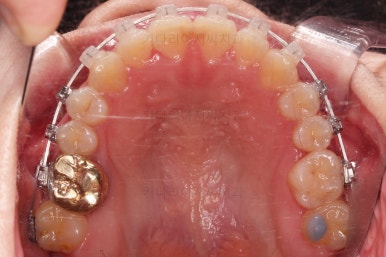

이번 부산교정 환자분은 교정치료 첫 단꼐로 악궁확장장치를 했는데요.

일반 확장 장치로는 불가하다는 판단이 되어 미니스크류를 활용한 악궁확장장치(MARPE)를 해주었어요.

저희 부산교정 키다리아저씨치과에서는 수십가지 분석을 통해 악궁확장이 정말 필요한지 아닌지를 판단하며 더하기 해서 일반 악궁확장장치(RPE)로 가능한지, 미니스크류를 이용한 악궁확장장치(MARPE)를 써야하는지 구분하여 치료를 하고 있습니다.

이번 환자분은 일반 악궁확장장치로는 불가하다는 판단에 미니스크류를 이용한 악궁확장을 시행했고요.

입천장에 장치를 3개월 가량 유지하는 동안 치아에 브라켓을 부착하여 가지런하게 해줍니다.